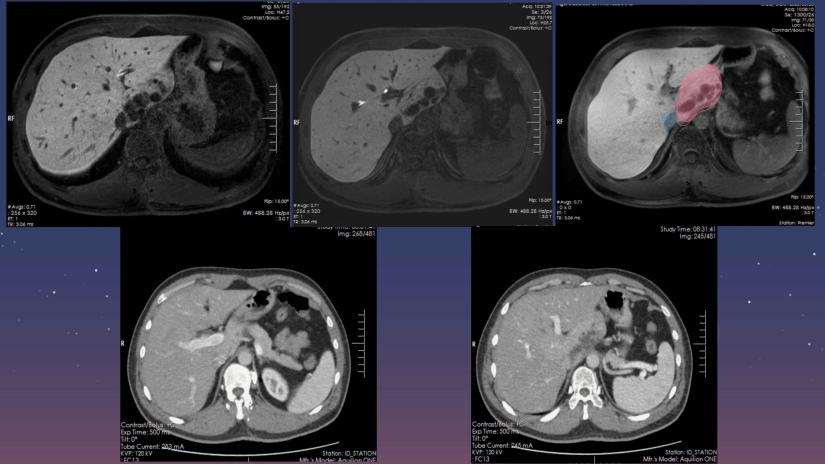

(视频2.腹腔镜下肝尾状叶切除)

(肝尾状叶术前影像学资料)